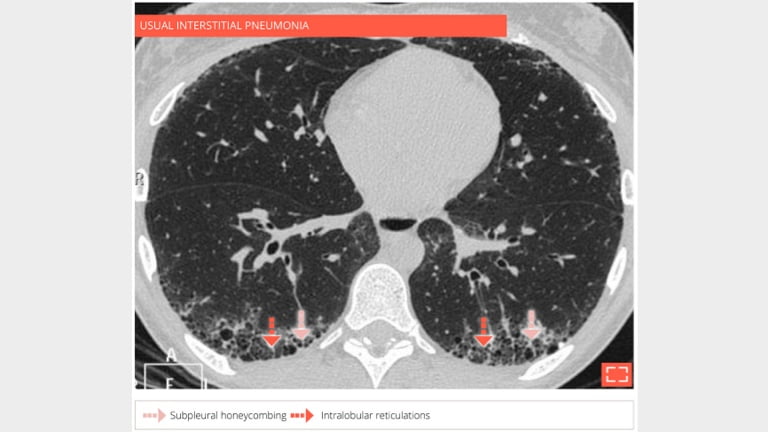

69-year-old man with usual interstitial pneumonia. Subpleural honey combing is associated with reticular pattern.